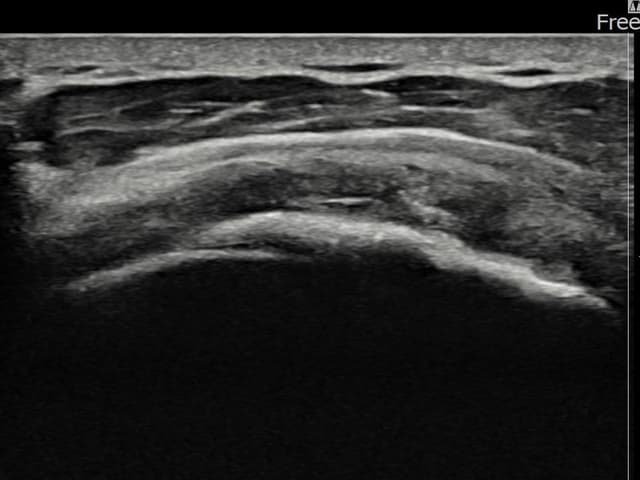

[촬영시기:23.07.18~23.09.14]

[어깨인대 축소봉합술] 좌측 어깨 광범위 파열로 수술을 권유받았으나 비수술 치료를 원해 내원하셨습니다.